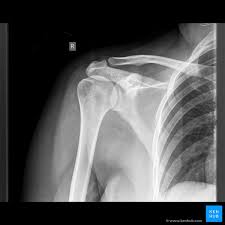

Plain Film X Ray Principles Interpretation Teachmeanatomy